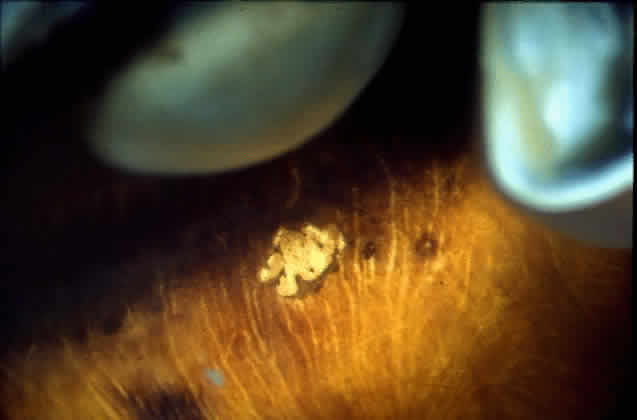

in a healthy globe.17–20 Drusen, ophthalmoscopically visible deposits present between the RPE basement

membrane and the inner collagenous layer of Bruch's membrane, are

membrane thickness.  Fig. 9. Solitary nodular drusen (arrow) resting on inner surface of Bruch's membrane. (H & E, × 63) Fig. 9. Solitary nodular drusen (arrow) resting on inner surface of Bruch's membrane. (H & E, × 63)